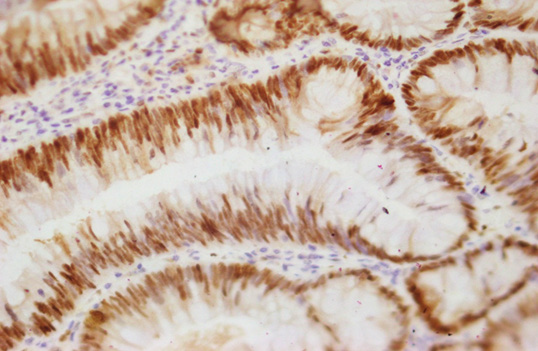

Photomicrograph

Figure 14: Photomicrograph of Hyperplastic polyp Ki-67 expression: Positive (Case No: 38, IHC X 40x).